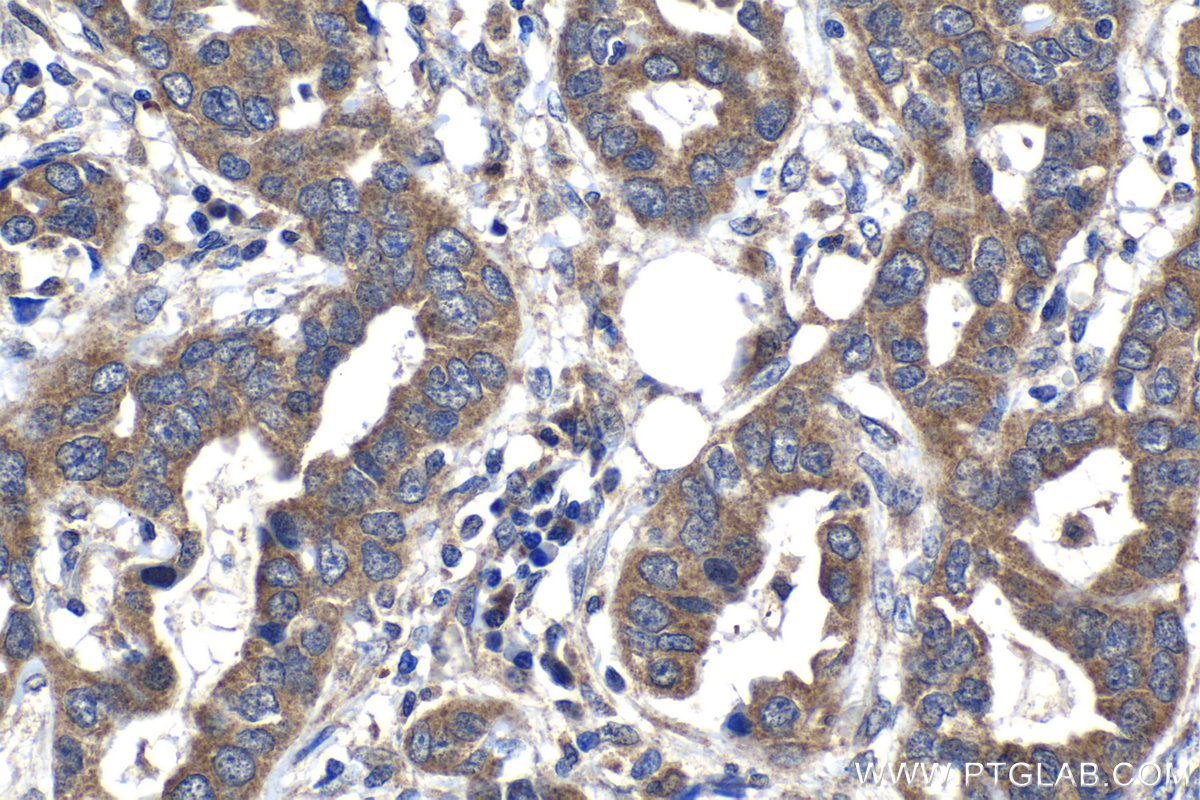

| Positive IHC detected in | human liver tissue, human kidney tissue, human lung cancer tissue Note: suggested antigen retrieval with TE buffer pH 9.0; (*) Alternatively, antigen retrieval may be performed with citrate buffer pH 6.0 |

| Immunohistochemistry (IHC) | IHC : 1:250-1:1000 |

22471-1-AP targets SPDYC in IHC, ELISA applications and shows reactivity with human samples.

SPDYC(Speedy protein C), also known as RINGOC and Ringo2, promotes progression through the cell cycle via binding and activation of CDK1 and CDK2. Downregulation of SPDYC inhibits cell growth, reduces the fraction of cells in G1, and increases the S and G2 populations(PMID: 18802405). SPDYC is involved in the spindle-assembly checkpoint and required for recruitment of MAD2L1, BUBR1 and BUB1 to kinetochores(Uniprot).